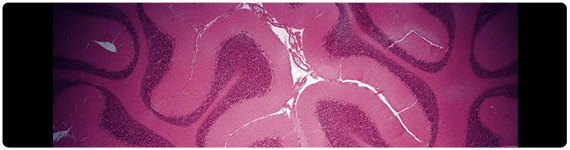

El estrés oxidante ha sido implicado en la patogénesis de una variedad de desórdenes neurodegenerativos, incluyendo esclerosis lateral amiotrófica, enfermedad de Alzheimer, enfermedad de Huntington y la enfermedad de Parkinson (PD, por sus siglas en inglés). PD proporciona un excelente paradigma para explorar el papel de los oxidantes en el desarrollo de la enfermedad –bioquímica oxidante, agregación de proteína y degeneración neural están presentes en el análisis postmortem de los cerebros de pacientes. PD, el segundo desorden degenerativo más común, es tipificado por afectaciones motoras que incluyen temblor en descanso, rigidez muscular, inestabilidad y bradiquinesia. La pérdida selectiva de neuronas dopaminérgicas ocurre en la pars compacta de la substantia nigra, llevando a niveles muy reducidos de dopamina en el striatum (núcleo estriado), y es acompañada por la presencia de inclusiones citoplásmicas conocidas como cuerpos de Lewy (LBs, por sus siglas en inglés) en regiones del tallo cerebral y las neuronas dopaminérgicas de la pars compacta de la substantia nigra.